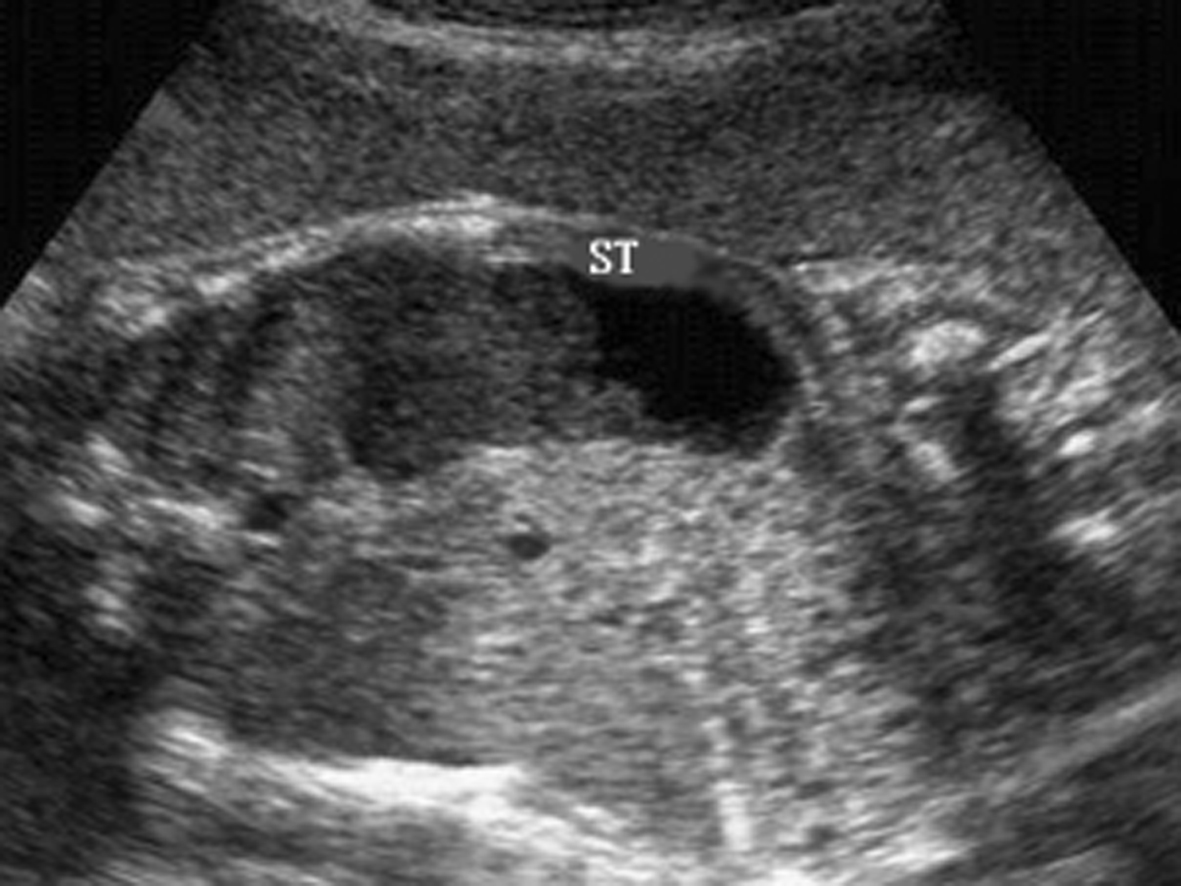

超声主要表现为胃泡增大,伴有羊水过多。胃蠕动增强,可见逆蠕动。胃食道反流导致食道扩张(图1)。

图1幽门梗阻声像图